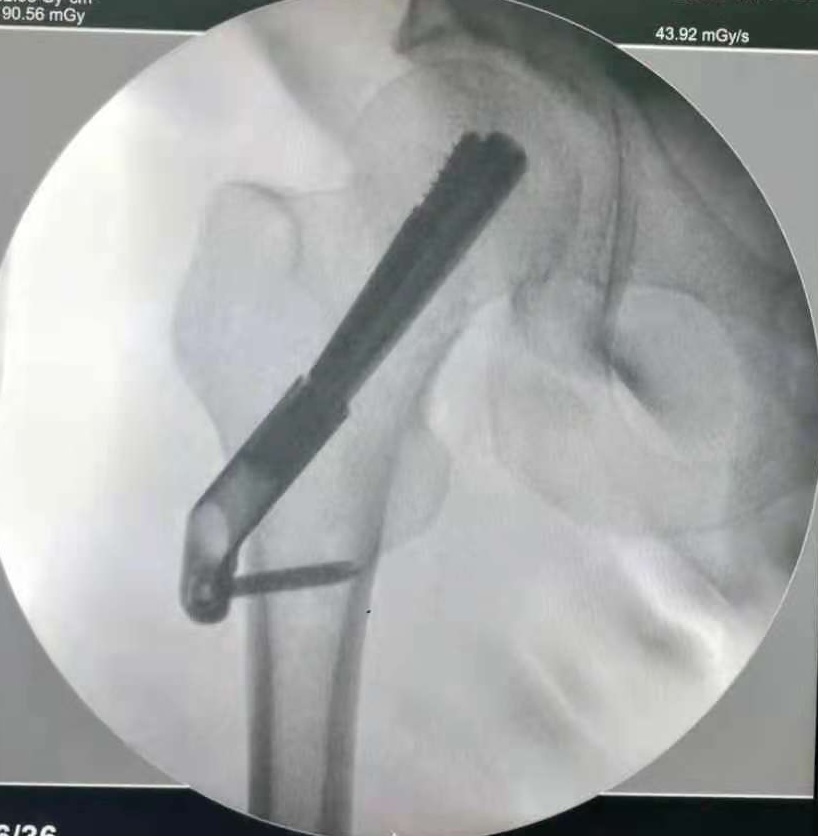

术前麻醉后给予骨折牵引复位成功,通过克氏针穿刺精确定位,将防旋交叉钉系统准确植入。

图3 精确定位并置入防旋交叉钉系统